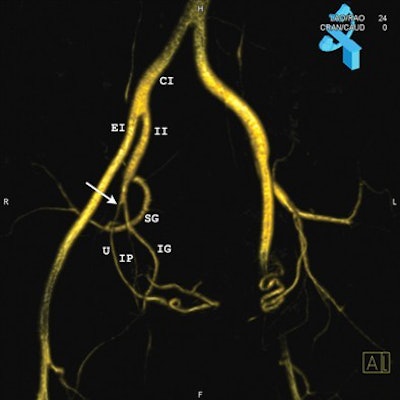

| Images in a 44-year-old woman. Above, 3D-reconstructed contrast-enhanced MR angiographic image from the pre-embolization study. The model was rotated to a 24° left obliquity for demonstration of the origin (arrow) of the right uterine artery (U) (routine oblique view). Upper right corner of the image shows the corresponding C-arm position and the obliquity angle (24° left oblique). Below, digital subtraction angiography (DSA) image in the same patient shows the corresponding angiographic projection and clear demonstration of the origin (arrow) of the right uterine artery (U). Additional arteries visualized include the common iliac (CI), external iliac (EI), inferior gluteal (IG), internal iliac (II), internal pudendal (IP), obturator (O), superior gluteal (SG), and superior vesical (SV). Both images courtesy of the Radiological Society of North America. |